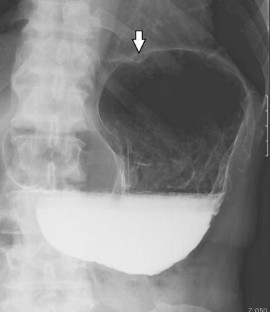

Fig. 2